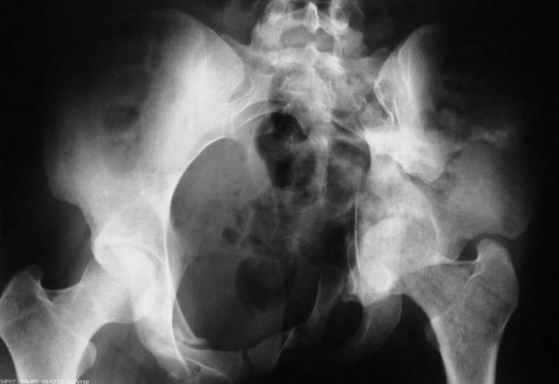

Рентгенограмма до операции

В заключении будет демонстрация операции больной 27 лет с давностью травмы более 2,5 мес.(3D прилагается) Убедительная просьба до 24.11.2008 всем желающим сообщить по адресу: pelvistrauma@mail.ru следующие данные: 1. Ф.И.О. 2. Должность и место работы 3. Контактный телефон. Семинар состоится на базе ГКБ №15 по адресу: г.Москва, ул. Вешняковская, д.23. административный корпус, IV этаж, 1 травматологическое отделение